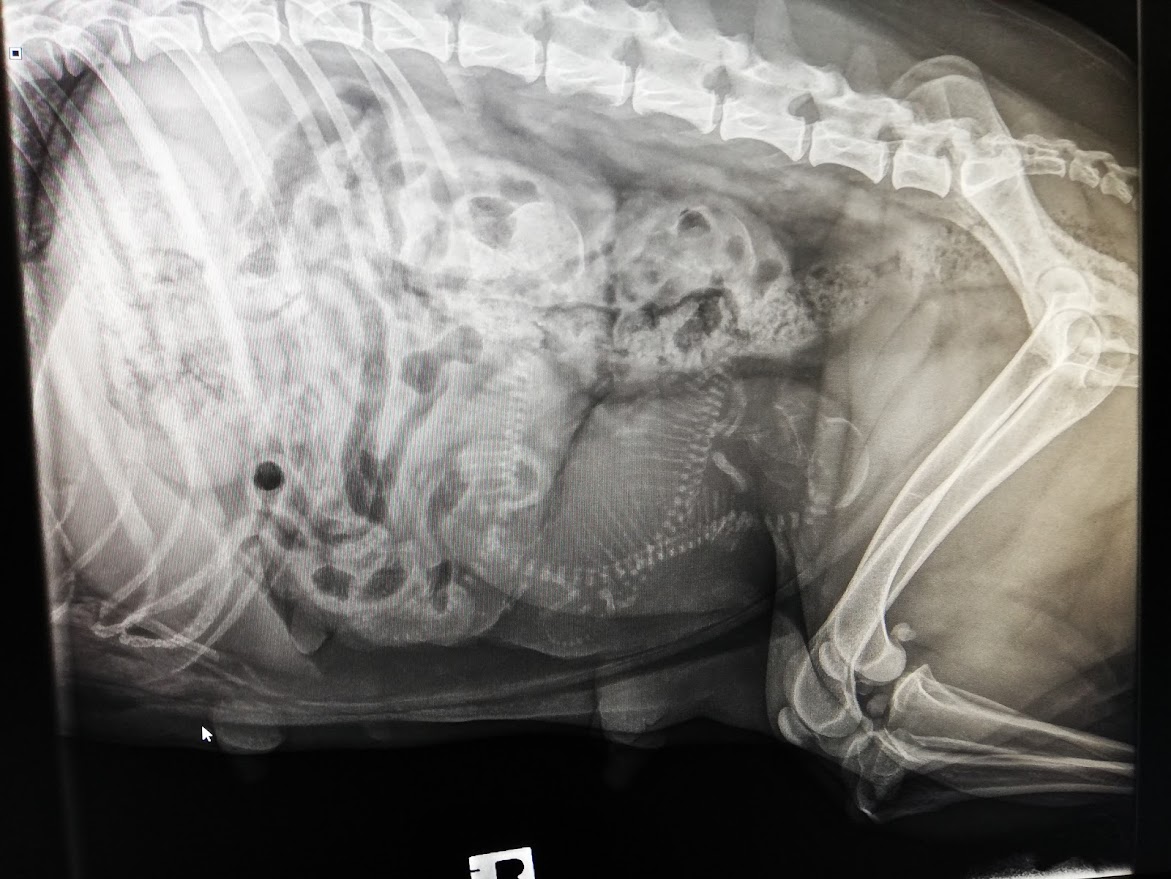

Tiineysröntgen 19.2.2024

Kävimme pipsan kanssa tiineysröntgeissä. Kovin montaa pentua ei näkynyt, mutta toivotaan että ensi viikon synnytys menee hyvin.